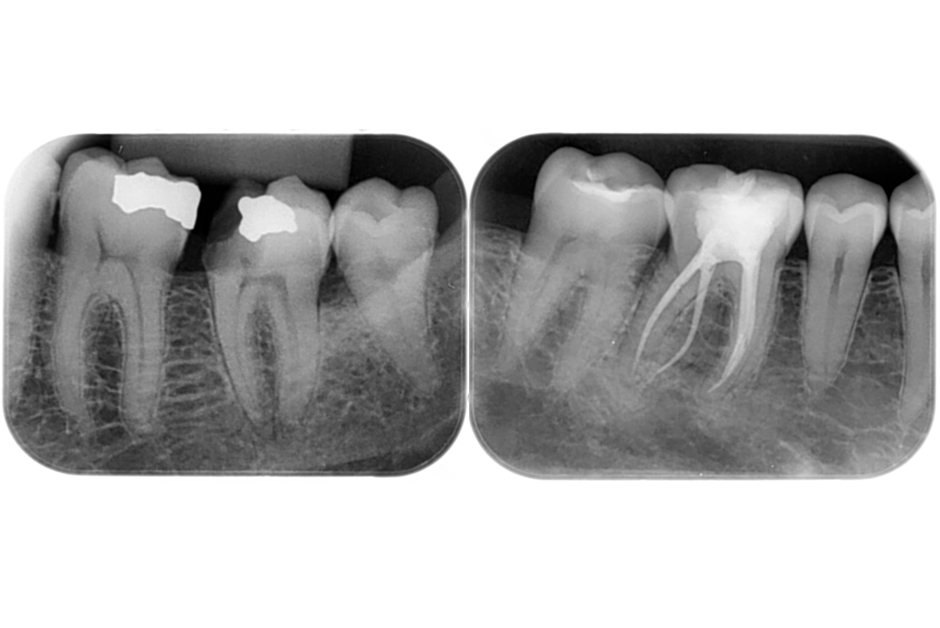

Endodoncia

En N&S Estudio Dental sabemos que conservar tus dientes naturales siempre es la mejor opción. La endodoncia, conocida también como “tratamiento de conducto”, es un procedimiento que permite salvar piezas dentales gravemente dañadas o infectadas, evitando su extracción.

Este tratamiento consiste en eliminar la pulpa dental afectada (el tejido interno donde se encuentran los nervios y vasos sanguíneos), desinfectar cuidadosamente el conducto y sellarlo para prevenir futuras infecciones. Todo se realiza con tecnología de última generación que nos permite trabajar con precisión, comodidad y rapidez, reduciendo al mínimo las molestias.